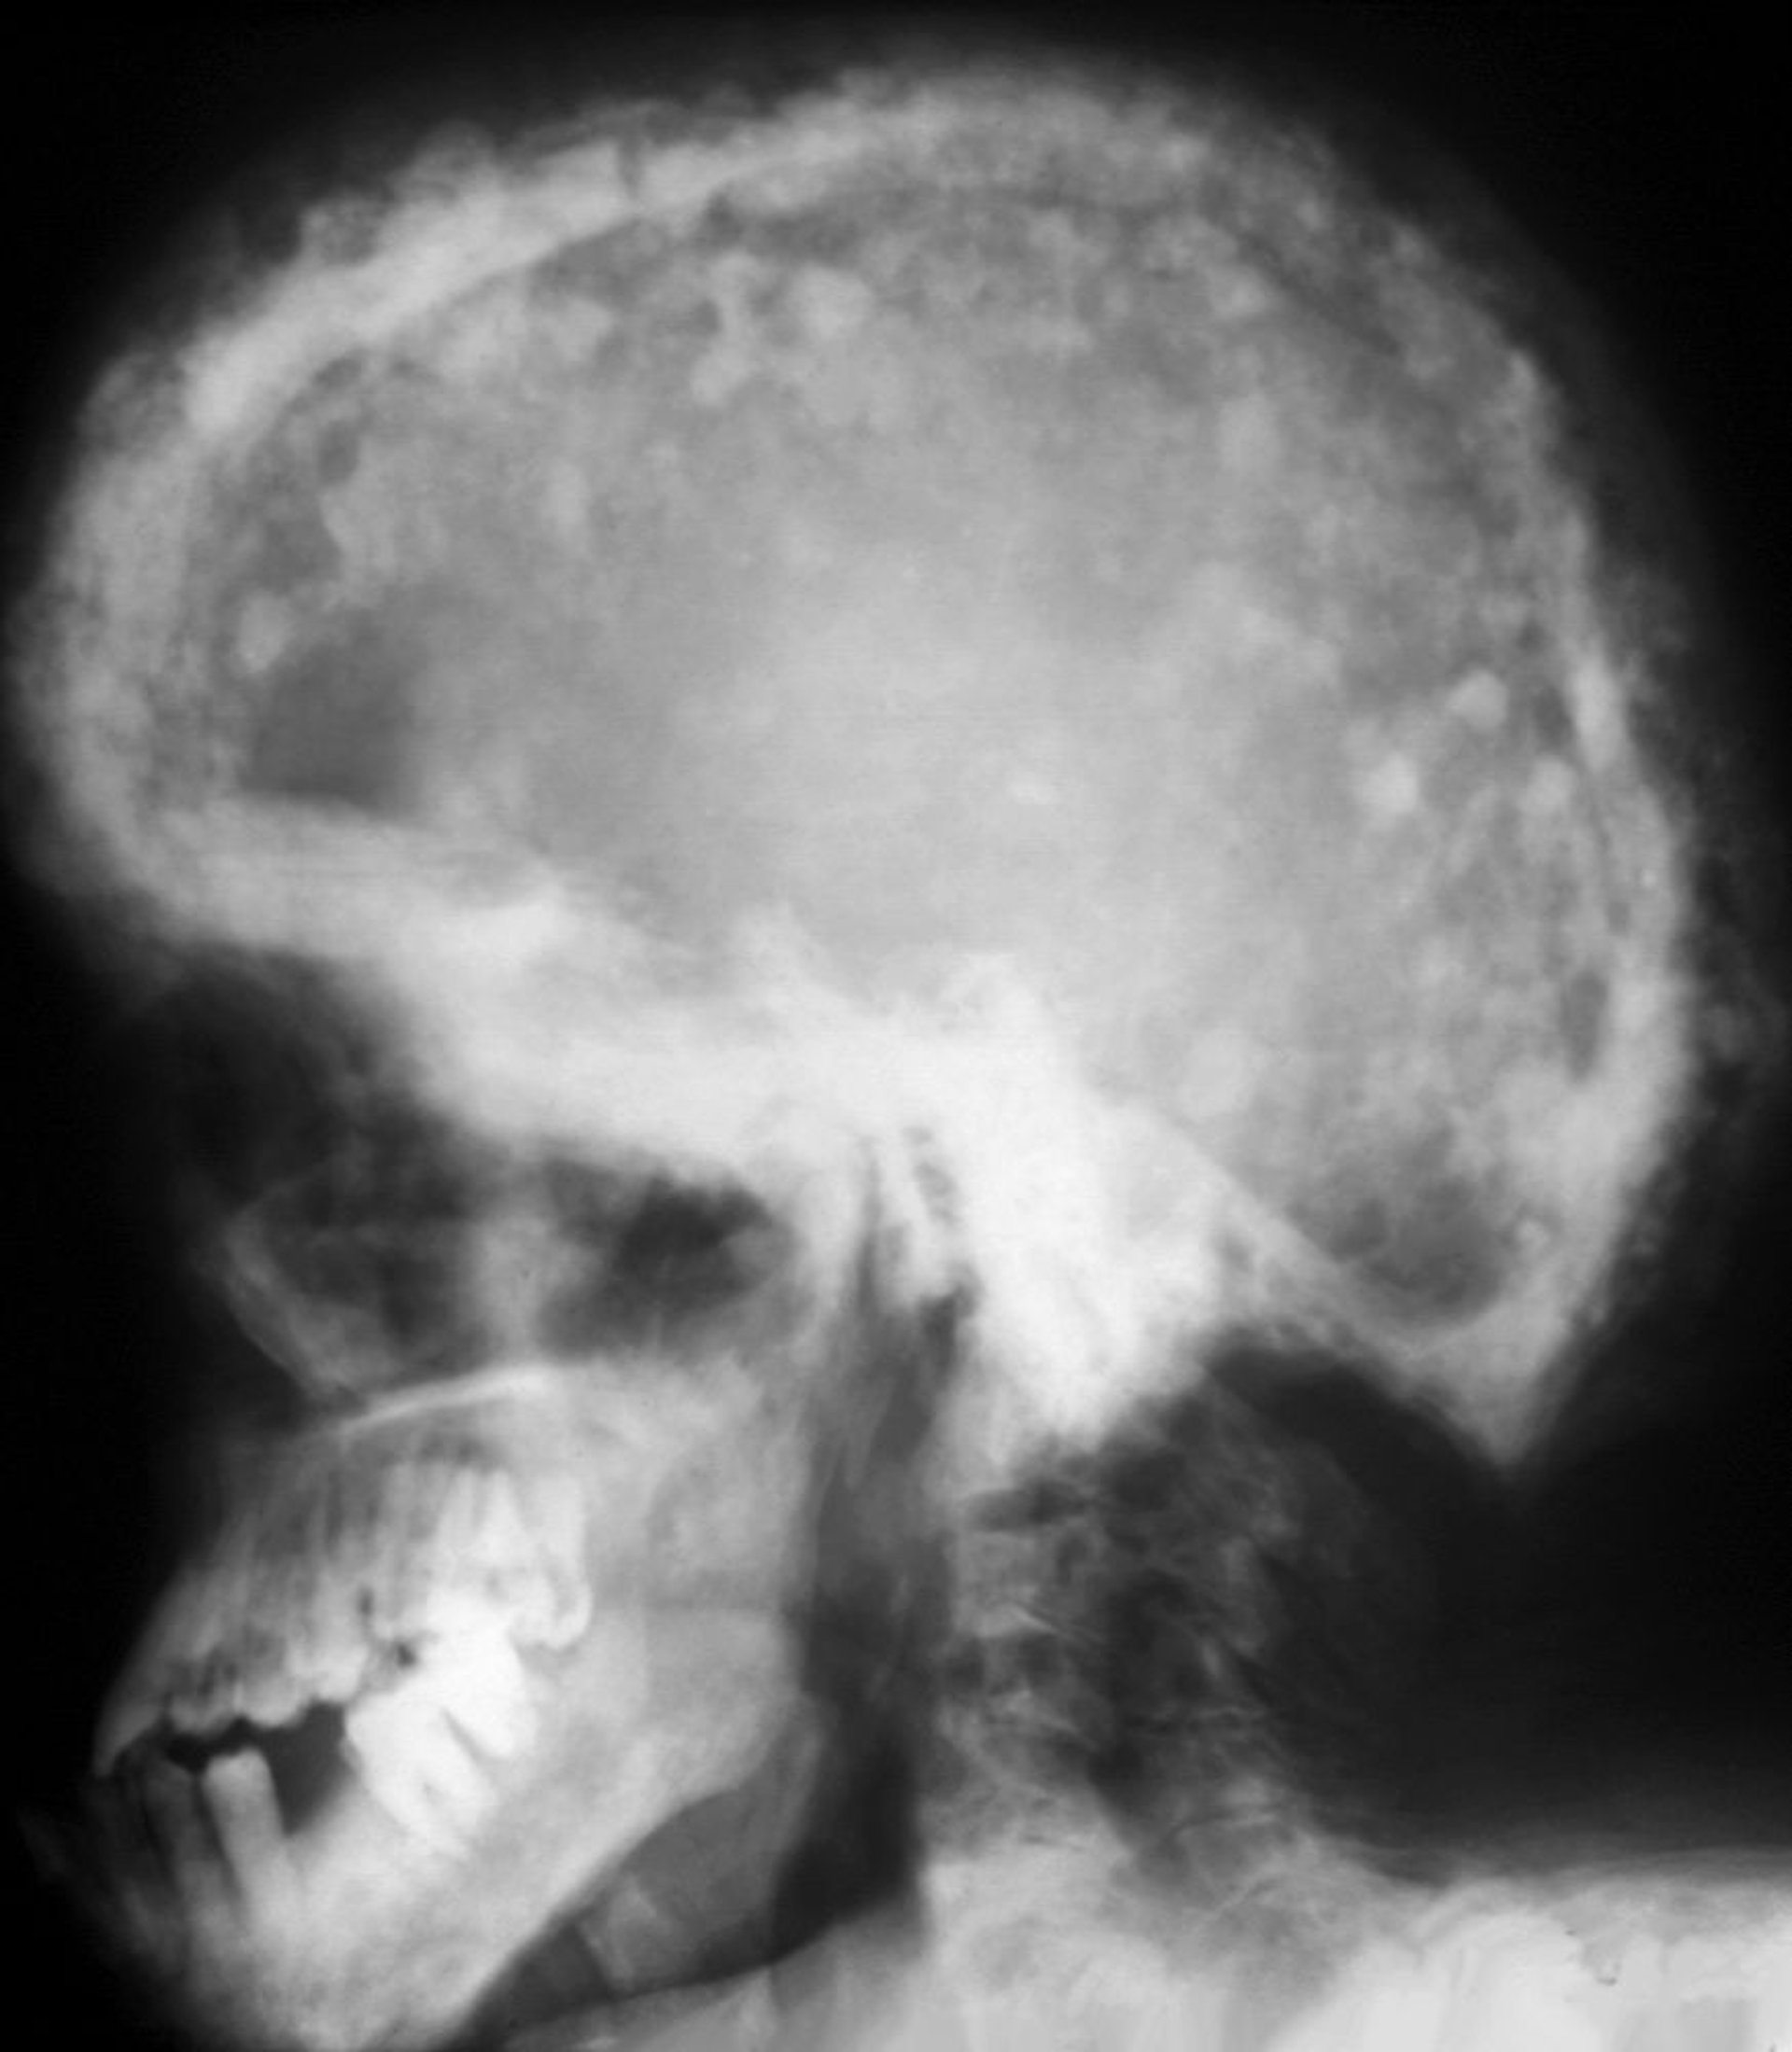

パジェット病における頭蓋骨のX線

このX線写真では,硬化が進んだ領域と透過性が増した領域が混在する典型的なモザイクパターンがみられる。このcotton-wool patchは頭蓋冠の肥厚に起因する。